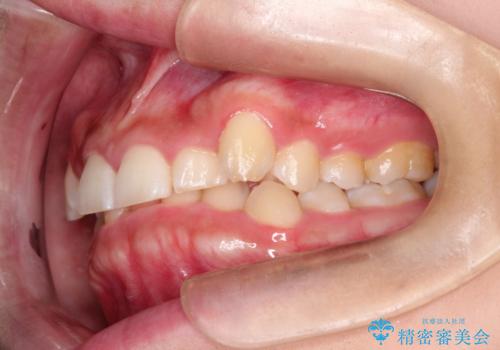

- 前歯の凸凹と深い噛み合わせを主訴に来院されました。

下の前歯が見えないほどのディープバイト症例でした。

ワイヤー矯正にて下顎前歯の圧下と臼歯部の挺出を効率的に行うことができました。